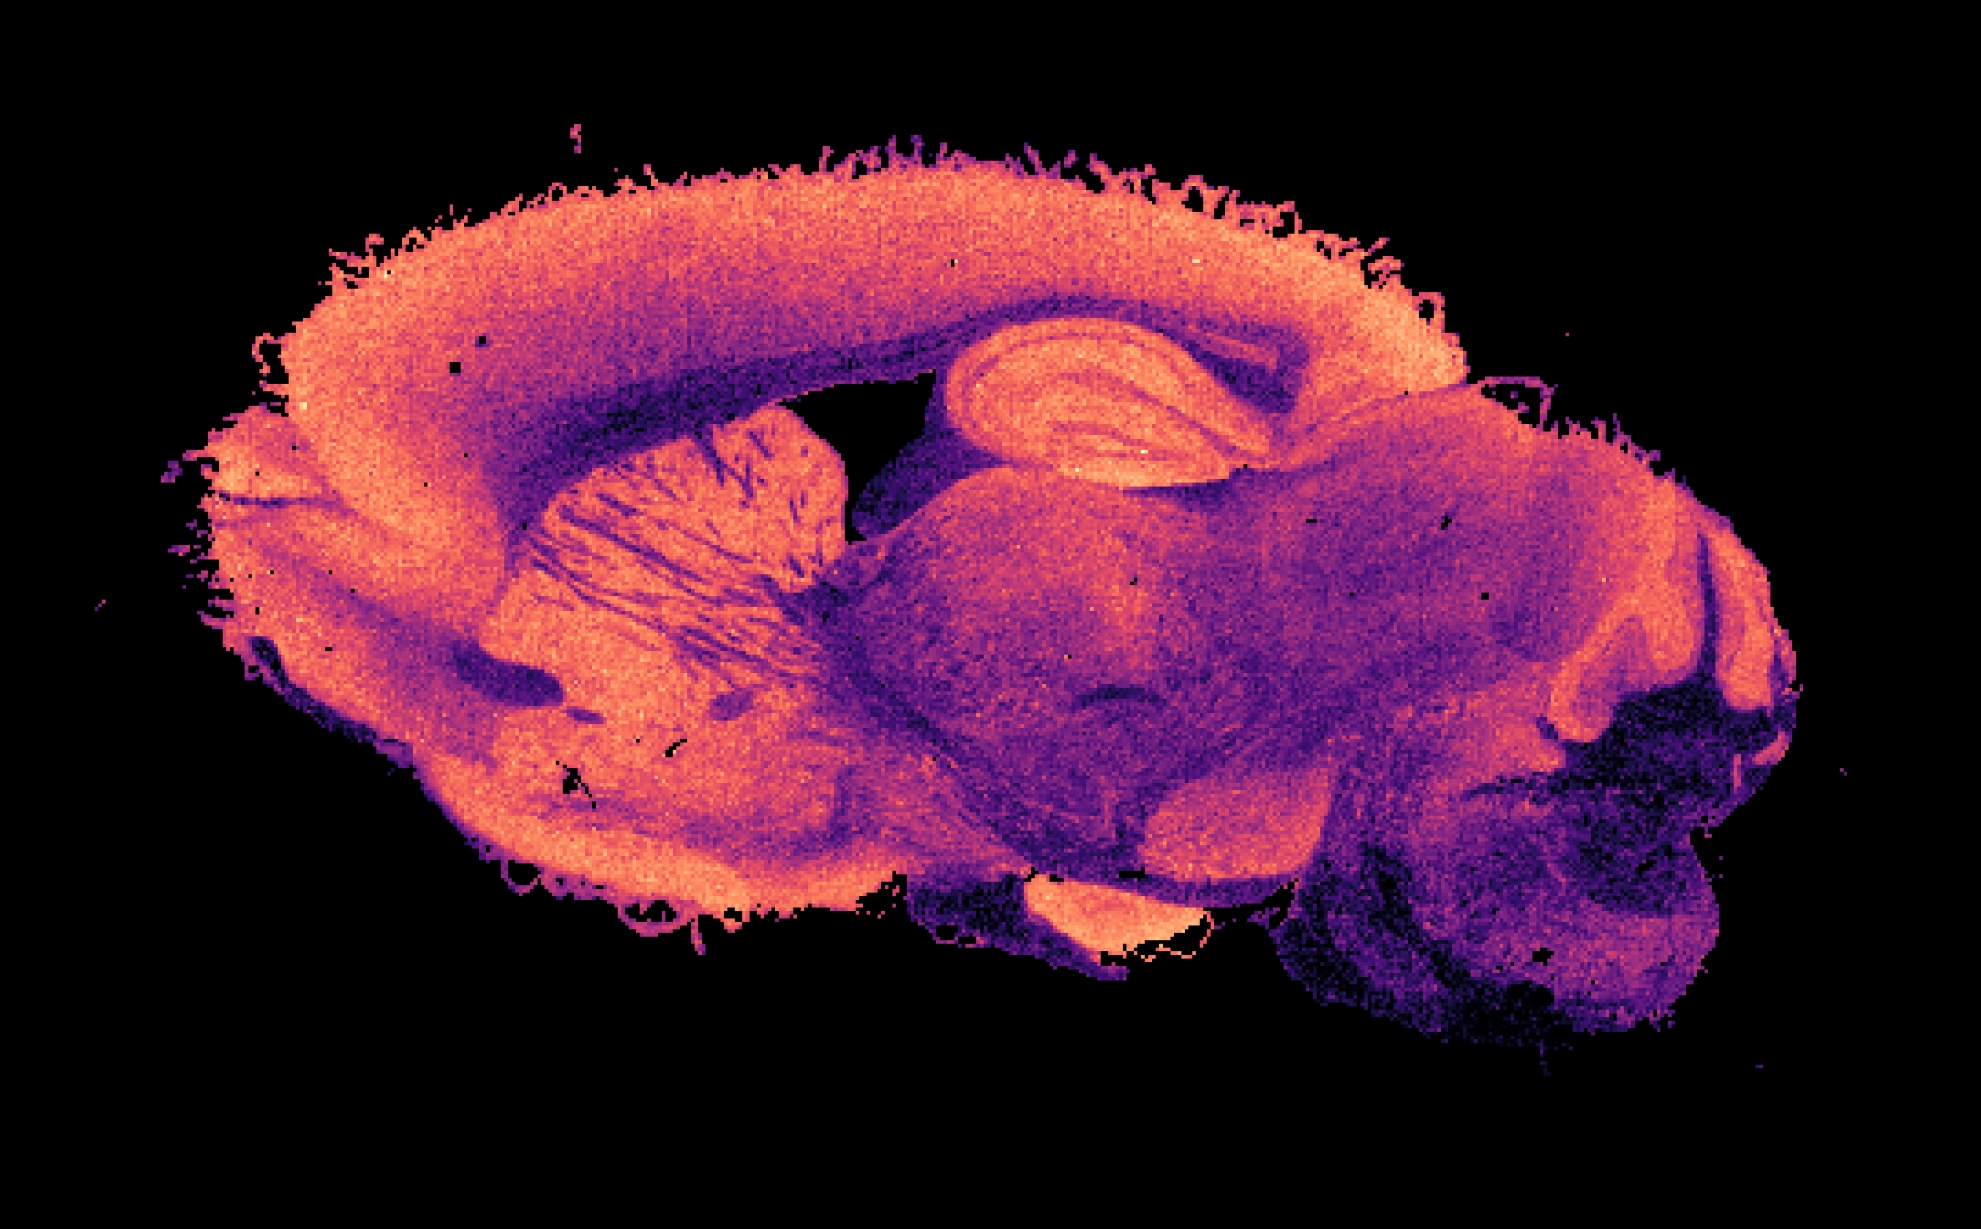

Hospital and research laboratories can already tell quite a lot about which molecules are present in a complex fluid like a blood sample. They do this by using mass spectrometry, among other methods. This involves measuring the mass of molecules, looking at how many of those different masses are present. In the case of a piece of tissue, mass spectrometry imaging is used to tell exactly where these molecules are located. You can see the result of this in the image above this article. However, this still doesn’t tell you everything. Two molecules can weigh the same but have completely different structures and functions. Therefore, it is also necessary to say something about the structure of each molecule. Only then do you know for certain which one you are dealing with.